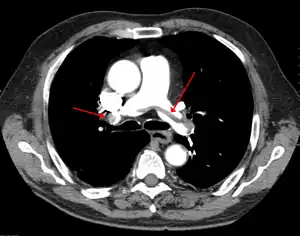

| Chest spiral CT scan with radiocontrast agent showing multiple filling defects both at the bifurcation ("saddle" pulmonary embolism) and in the pulmonary arteries | |

CT pulmonary angiography (CTPA) is a pulmonary angiogram obtained using computed tomography (CT) with radiocontrast rather than right heart catheterization. Its advantages are that it is accurate, it is non-invasive, it is more often available, and it may identifying other lung disorders in case there is no pulmonary embolism. The accuracy and non-invasive nature of CTPA also make it advantageous for people who are pregnant.[52]

Assessing the accuracy of CT pulmonary angiography is hindered by the rapid changes in the number of rows of detectors available in multidetector CT (MDCT) machines.[53] According to a cohort study, single-slice spiral CT may help diagnose detection among people with suspected pulmonary embolism.[54] In this study, the sensitivity was 69% and specificity was 84%. In this study which had a prevalence of detection was 32%, the positive predictive value of 67.0% and negative predictive value of 85.2%. However, this study's results may be biased due to possible incorporation bias, since the CT scan was the final diagnostic tool in people with pulmonary embolism. The authors noted that a negative single slice CT scan is insufficient to rule out pulmonary embolism on its own. A separate study with a mixture of 4 slice and 16 slice scanners reported a sensitivity of 83% and a specificity of 96%, which means that it is a good test for ruling out a pulmonary embolism if it is not seen on imaging and that it is very good at confirming a pulmonary embolism is present if it is seen. This study noted that additional testing is necessary when the clinical probability is inconsistent with the imaging results.[55] CTPA is non-inferior to VQ scanning, and identifies more emboli (without necessarily improving the outcome) compared to VQ scanning.[56]

On CT scan, pulmonary emboli can be classified according to level along the arterial tree. -

Segmental and subsegmental pulmonary emboli on both sides -

CT pulmonary angiography showing a "saddle embolus" at the bifurcation of the main pulmonary artery and thrombus burden in the lobar arteries on both sides.